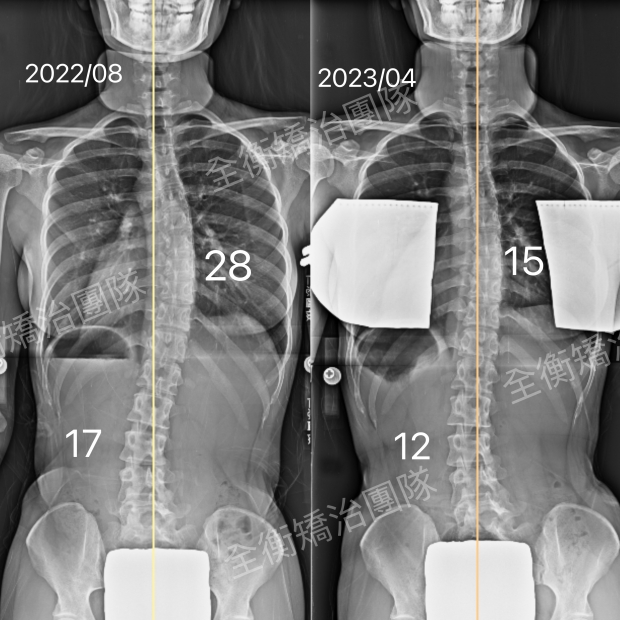

6594X光对比.jpg

22歲成年人側彎,8個月,28度進步至15度,度數減少46%

22歲胸椎彎28度女生,

認真穿戴施羅斯背架並確實執行復健運動,

8個月後的X光追蹤,帶來了很大驚喜:

胸椎主彎從28度進步到15度,度數減少了46%!